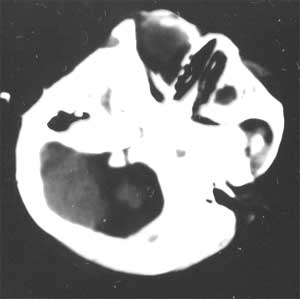

通过脑ct看医生说比较严重 ct检查报告是:右侧基底节区低密度灶,脑沟裂明显增宽,脑室系统清度扩大,中线结构无移位。 ct诊断:1。右侧基底节区缺血性改变 2。脑发育不良

幕上幕下脑室、脑池、脑沟均见扩张积液,考虑脑发育不良。片子质量不好,前囟门似乎偏小,颅骨骨缝不知是否有闭合。9个月幼儿,头围应该不小于40厘米,请测量头围周径。应该没有胼胝体发育不良。至于“右侧基底节区缺血性改变”,片子质量差,看不清楚。

从ct片看1大脑纵裂增宽2侧脑室扩大3蛛网膜下腔增宽 应考虑1胼胝体发育不良,2脑发育不良或萎缩(两周前一般无临床意义应称蛛网膜下腔增宽或外周性脑积水)

纵观以上ct片考虑胼胝体发育不良之诊断欠依剧,还应结合临床,是否有sah或hie等,但脑发育不全不能除外!

不同意胼胝体发育不良的诊断,现在ct表现为脑沟、脑池增宽,双测额骨内板下方带状液体影,双测侧脑室略扩大,我认为应诊断为1、脑发育不全。2、外部性脑积水。情况应该很严重。

粗看:1。双侧额颞顶叶均有不同程度萎缩,脑实质变薄,2。脑室系统对称性扩张,大脑沟裂增宽变深。3。双基底节区未见明确低密灶,胼胝体发育良好。综上所述考虑有:1)大脑发育不良;2)严重脑缺血缺氧性脑病后遗症?个人意见仅供参考。